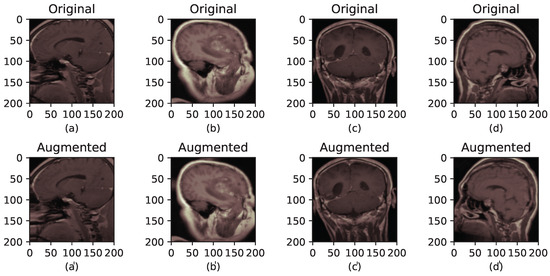

As depicted in Figure 5, a comparison of four sets of brain tumor MRI scans before and after image augmentation is illustrated. The first row displays a random selection of four images from the training set that have undergone preprocessing, as shown in Figure 4. The second row presents the same images after applying image augmentation.

Figure 5.

The brain tumor MRI before and after augmentation. (a–d) correspond to the original images, while (a′–d′) correspond to their augmented versions.

The experimental configuration included parameters: rotation_range = 10, width_shift_ range = 0.05, height_shift_range = 0.05, and horizontal_flip = True. The rotation_range controls the random angle range for rotation applied to each image. Meanwhile, width_shift_range and height_shift_range determine the images’ random horizontal and vertical shifts, respectively. The horizontal_flip parameter decides whether each image is randomly flipped horizontally, with a 50% probability.

It is crucial to emphasize that operations specified in ImageDataGenerator, such as rotation, shift, and flip, are randomly applied to each image. Therefore, each batch of generated images may exhibit variations. This stochastic process enhances the diversity of the training dataset, thereby strengthening the model’s ability to generalize effectively.